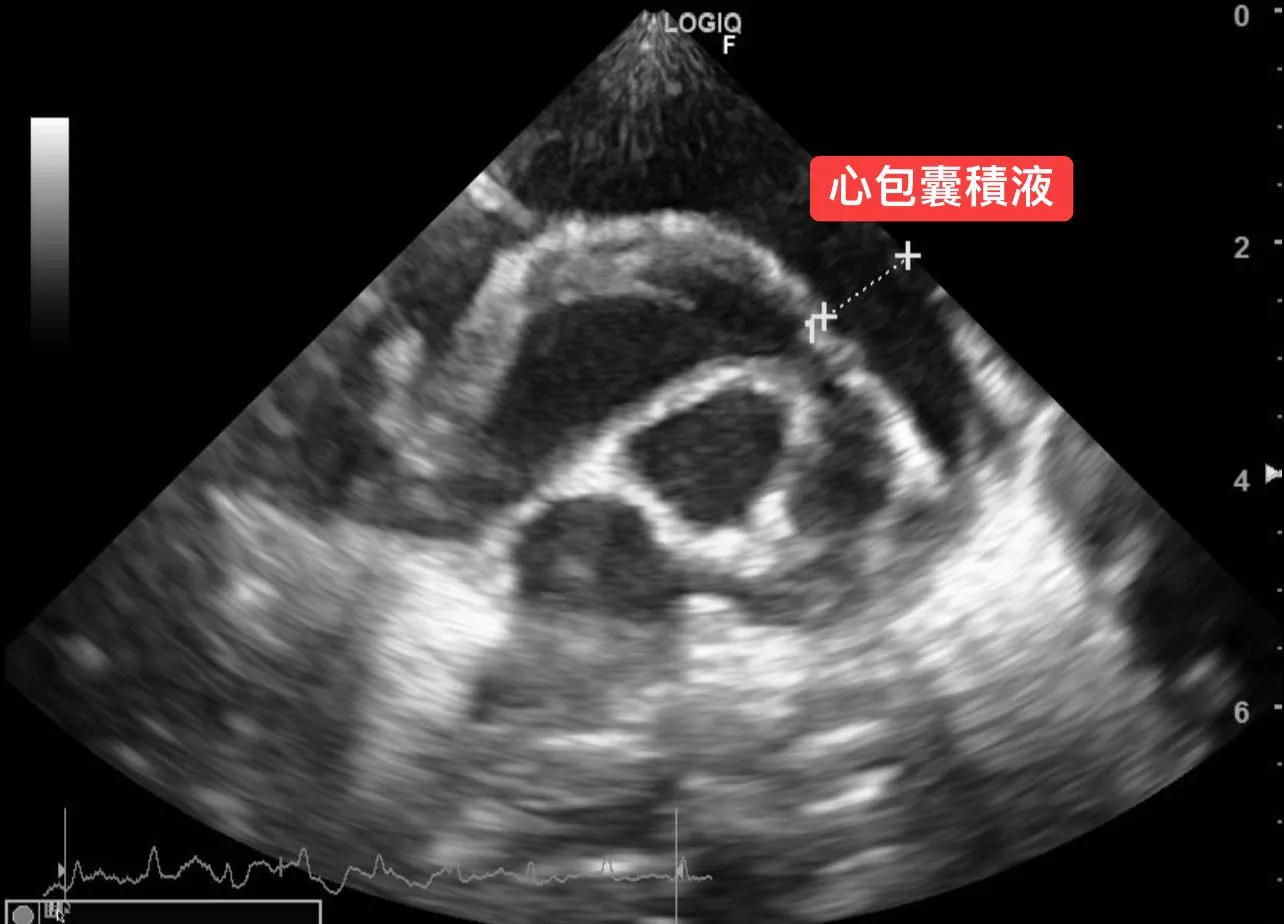

沒有心雜音的心臟病!?「心包囊積液」

4. 針對喘的問題,立刻安排心臟超音波檢查。

3. 心臟超音波檢查發現「大量心包囊積液」。